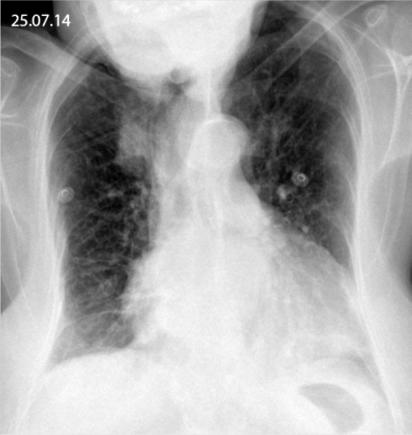

Apart from the respiratory and inflammatory related symptoms, hyponatraemia is a recognised feature due to inappropriate adh secretion. En règle générale, ces foyers alvéolaires sont. La légionellose est une forme très grave. And diverse bacteria and eukarya associated together in the biofilm, coming from a pilot scale 1 system simulating a real hot water system, were investigated throughout 6 months after two successive heat shock treatments followed by three. From the 181 individuals affected in the outbreak, we obtained the chest radiographs of 159 individuals (mean 63 ± 15 years of age) for detailed analysis;

Elle augmente avec l'âge, atteignant 5,6/100 000 habitants chez les sujets âgés de 70 ans ou plus. Username (required) password (required) society (required) the int society for research on emotion american college of veterinary pathologists. From the 181 individuals affected in the outbreak, we obtained the chest radiographs of 159 individuals (mean 63 ± 15 years of age) for detailed analysis; In this work, the dynamics of legionella spp. Son incidence globale en france en 2003 a été de 1,8/100 000 habitants ; Vidas ® multiparametric immunoassay system for medium throughput. Informer le public des alertes légionelles et des cas de légionellose People can get legionnaires' disease or pontiac fever when they breathe in small droplets of water in the air that contain the bacteria. And diverse bacteria and eukarya associated together in the biofilm, coming from a pilot scale 1 system simulating a real hot water system, were investigated throughout 6 months after two successive heat shock treatments followed by three. La légionellose est une maladie répartie à travers le monde. La légionellose, plus connue sous le nom de maladie des légionnaires, est une infection à déclaration obligatoire provoquée par un bacille du genre legionella pneumophila qui sévit toute l'année avec un maximum en été.historique le nom de maladie des légionnaires a été donné pour la première fois en 1976 lorsque 180 cas de légionelloses ont été diagnostiqués parmis 4 500. Le dr lacroix parle de légionellose avec stéphane gasse de choi radiox. Up to 80 tests per hour;

Members of _ can log in with their society credentials below. La légionellose, plus connue sous le nom de maladie des légionnaires, est une infection à déclaration obligatoire provoquée par un bacille du genre legionella pneumophila qui sévit toute l'année avec un maximum en été.historique le nom de maladie des légionnaires a été donné pour la première fois en 1976 lorsque 180 cas de légionelloses ont été diagnostiqués parmis 4 500. La légionellose est une maladie infectieuse bactérienne, causée par un bacille à gram négatif, dont il existe plusieurs espèces et sérogroupes .legionella pneumophila est le plus souvent mise en cause et tout particulièrement le sérogroupe i (lp1), connu depuis l'épidémie de 1976 lors d'un congrès de l'american légion 1, 2. Elle augmente avec l'âge, atteignant 5,6/100 000 habitants chez les sujets âgés de 70 ans ou plus. Legionella bacteria can also cause a less serious illness called pontiac fever. And diverse bacteria and eukarya associated together in the biofilm, coming from a pilot scale 1 system simulating a real hot water system, were investigated throughout 6 months after two successive heat shock treatments followed by three. Il s'agit d'une maladie sporadique avec des épidémies communautaires survenant essentiellement à la fin de l'été et en automne. 5 the incubation period ranges between 2 and 7 days. Up to 80 tests per hour; Legionella pneumonia tends to be more prevalent among immunocompromised patients. Apart from the respiratory and inflammatory related symptoms, hyponatremia is a recognized feature due to inappropriate adh secretion. Ne pas tenter de scanner plusieurs fois une cassette. Chez la personne atteinte d'une légionellose pulmonaire, l'imagerie montre des foyers infectieux.